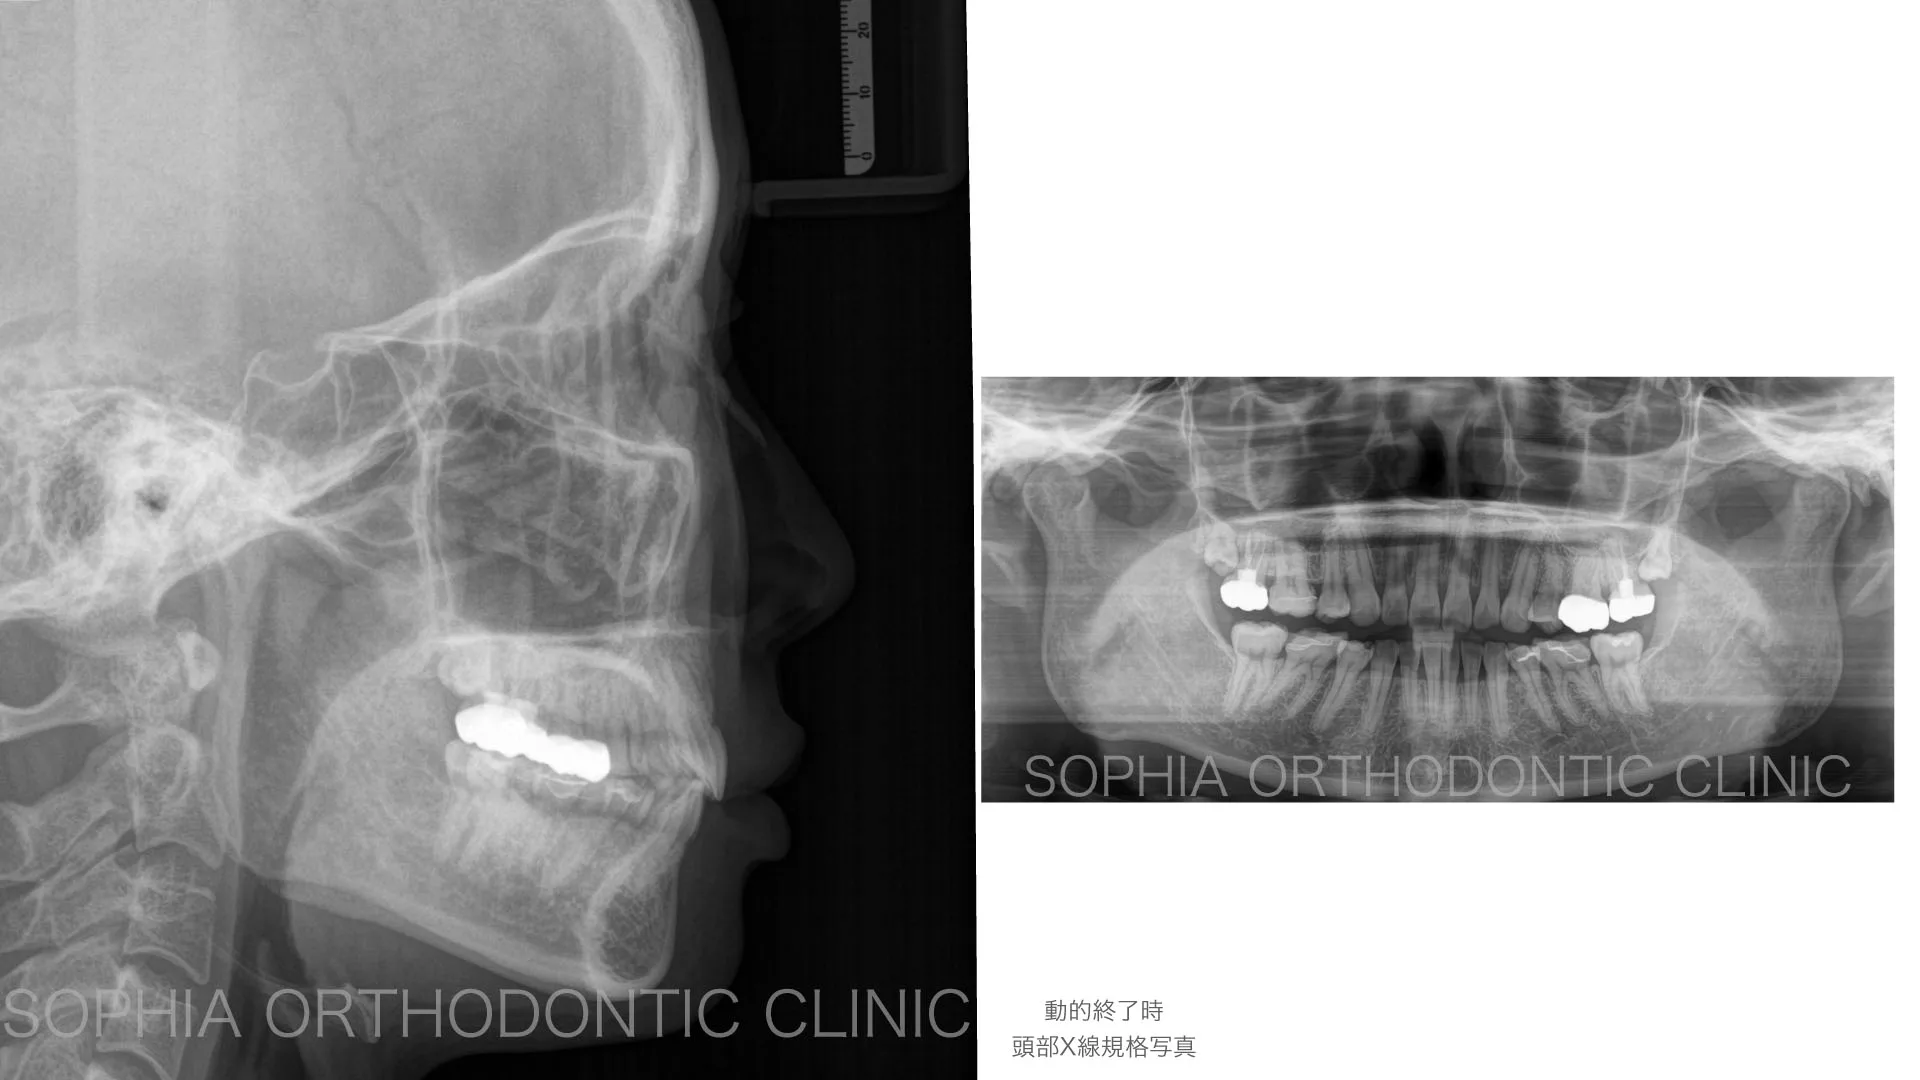

症例 前突